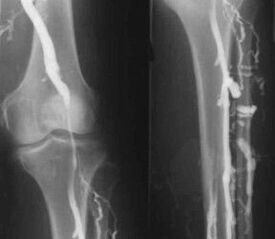

Najczęstszą instrumentalną metodą diagnostyki jest zastosowanie badania ultrasonograficznego naczyń żylnych nóg. Technika ta pozwala na wizualizację układu naczyniowego i określenie stopnia zaawansowania procesu patologicznego.

- Flebografia.